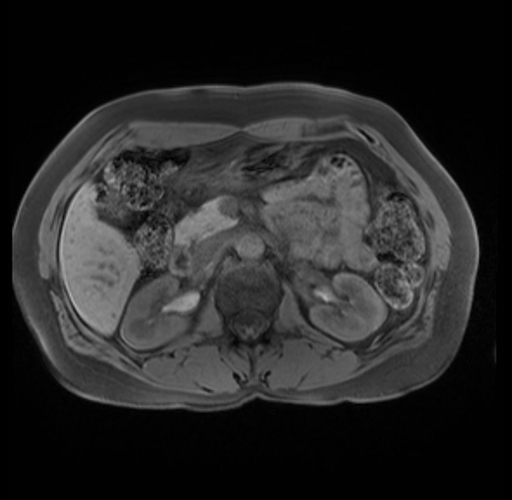

Imaging Analysis

Look through the patient's CT scan to identify any areas of concern for the necessary procedure.

Based on your CT findings, which issue(s) are present and would give reason for "planned slowing down moment(s)" in this case?